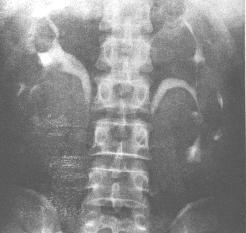

靜脈腎盂造影止痛藥腎病的腎臟表現是非特異性的,在仔細詢問病史的同時如臨床上出現腎病綜合徵急性腎功能衰竭、慢性腎功能衰竭以及高血壓、貧血腰痛或血尿尿液分析正常或有無菌性膿尿、血尿蛋白尿,(臨床表現可為輕度蛋白尿,也可為腎病綜合徵範圍蛋白尿可超過3.5g/d);CT掃描或靜脈腎盂造影可見患者出現部分和全部的腎乳頭壞死腎臟縮小腎盞變鈍等與慢性腎盂腎炎相似的改變,既可考慮本病診斷

2、放射學檢查主要是用靜脈腎盂造影和CT掃描來診斷或排除止痛藥腎病,25%~40%的患者可以出現部分和全部的腎乳頭壞死;其餘的大多數患者則表現為腎臟縮小腎盞變鈍、與慢性腎盂腎炎相似靜脈腎盂造影對缺血性腎病診斷有一定的限制性(敏感性低並對腎功能受損的患者有潛在的腎毒性)。